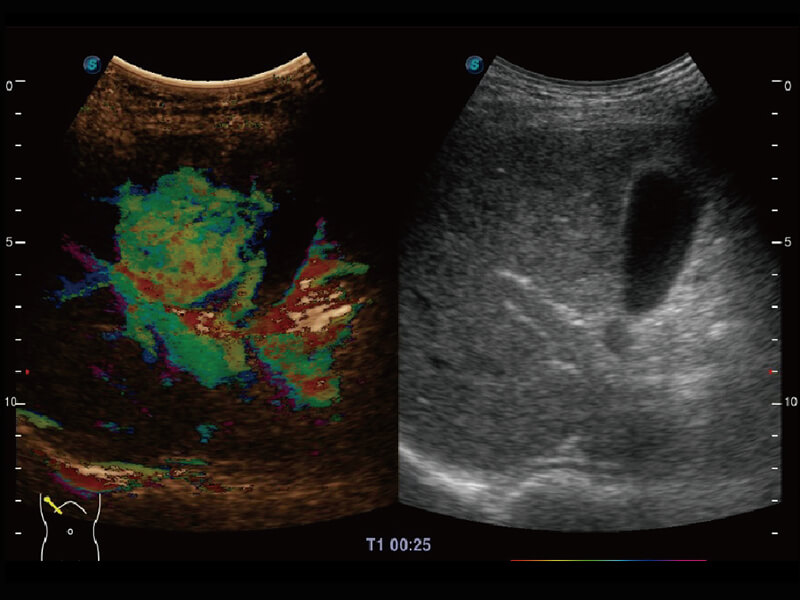

成像功能

性能优异的硬件架构,极大提升超声系统的运行效率和数据处理能力。相比以往超声成像系统,Wis+平台为您带来极快的响应速度和成像帧频,提升检查流畅度。

S60探头工艺,从前端信号处理每一个环节采集无损声学数据,真实还原组织原貌,再现解剖细节。